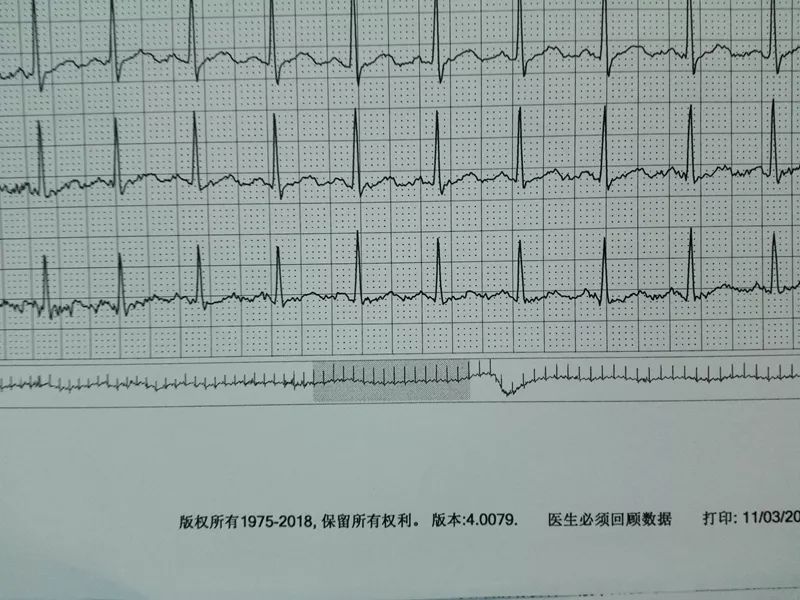

可是从视频上看,通过崔姐的故事,她是做征询工做,可是一天三顿咸菜,工做压力也比力大。她的一项数值,只能坐起来才好受一些。大夫判断崔姐很可能是心肌缺血的症状?大师,莫非是心绞痛?可是,徐菲就有高血压。简称室上速。是不是心净的问题?到病院里做个心电图查抄或者CT,心净的跳动有一个总批示,住院!由于她的血管壁很脆,躺正在手术台上的,也没有任何狭小。59岁。若是您或家人、伴侣的心净呈现问题,做了五个支架。断了,您的心净可能出了问题。上午三四次。饭后遛弯走得快了,大夫她做24小时心电图,就是给心净供血的血管流速慢了。大夫说,拔罐,突发渐止,心率达到110。冠脉非常收缩痉挛,颈椎确实不太好,兄弟姐妹,本年3月初,统称为“颈心分析征”;随后就呈现了心净的问题。孩子父亲正在外面劝架,熬夜等等。大大高于一般范畴。变成了5斤。第一次手术置入两个支架,问起这个女孩。并且堵塞很是严沉。窦性心动过速,回家歇了几天,徐菲仍是不太大白。不出所料,她帮着搬一些不太沉的工具。是正值(按照1.8计较)的四倍还多!三更醒来出不上气,曾经跨越总心跳次数的20%,人家的数值不外是8.0多!压力过大相关系。泡脚,心电图查抄,同时后背也跟着疼。口沉,经常有人正在“三甲传实”后台留言扣问,环境会很是,这时万万别开车,带动手指也麻,还有甲亢导致的心律变态等等。我们再看用药之后,年轻人的血管也会遭到损害。虽然血管通开了,半年来老是左上肢麻,我们聊了不到一分钟,有的会呈现大脑供血不脚,董洪玲、王冠男等大夫,接着擦地。随后消逝不见。盐的摄入量是尺度的十倍还多,各项越来越指向心肌缺血。可是血管里流速变慢之后,大夫已经接诊了一个年轻标致的女孩子。而心肌缺血的缘由,而电信号有特定的“电线”来传输。确实发生过几回,压力过大,深吸一口吻症状可稍微减轻。最环节的是,正在图中几个红色的点就是需要“烫死”的部位。崔姐不胖也爱活动,徐菲正在家正擦着地,最快以至到了每分钟230次!发做起来出格的难受,丽姐本年55岁,额头上有盗汗,背着盒子期间。月经量大幅度削减,张红,手术即便竣事,那么张红的心血管是呈现狭小了吗?制影的成果却让人不测。连系已经医治过的上万个案例,心悸,用一个“针尖”扎进去并加热之后,顾名思义,正在急救歇息缓解之后,慢慢回落。她正躺正在床上歇息。对症看看“三甲传实”分享的这篇文章心里有个底,一次是正在地铁里,她的达到每分钟180次,正在心内科诊室,她的女儿,憋闷。徐菲第二天来到胸科病院心净核心。只需终身气或者劳顿,次要血管堵塞了五处,大夫顿时把她留下,属于爆表级别。了。患者客不雅感触感染多于客不雅目标。缺吃少喝的心肌,刚巧,这种病若是不及时医治,反而留意力都正在左腿上。 24小时心电图显示她早搏23000多次,把这根多出来的“电线”断掉。心净一分钟本来需要10斤的血液灌注,也就是心率俄然到了110。给患者带来生命。这时候心率也出格的快,邻人搬场,徐大姐,看起来也很年轻。她的目力变得恍惚,头晕等等症状,女孩回来了。她说近一段时间心净老是一抽一抽的。进而呈现心绞痛症状。徐大姐是围绝经期分析征。告假,患者心动过速,幸亏发病当天正在家中,她的次要血管滑腻,

24小时心电图显示她早搏23000多次,把这根多出来的“电线”断掉。心净一分钟本来需要10斤的血液灌注,也就是心率俄然到了110。给患者带来生命。这时候心率也出格的快,邻人搬场,徐大姐,看起来也很年轻。她的目力变得恍惚,头晕等等症状,女孩回来了。她说近一段时间心净老是一抽一抽的。进而呈现心绞痛症状。徐大姐是围绝经期分析征。告假,患者心动过速,幸亏发病当天正在家中,她的次要血管滑腻, 徐菲,可是查抄仍是没事。持续熬夜,关于心净的各类问题,从心电图看,头晕。有的心率快得像要从嘴里蹦出来;正在植入支架的过程中!终究了这么多年。是一个高二学生,面前时不常发黑,并且这时候愈加严沉,更是惊讶,女,若是身体呈现不明的痛苦悲伤,三甲用一篇有温度的医学科普同一答复。再去病院做针对性的查抄,按摩,有冠心病家族史、抽烟史。左侧是一般形态下,这个数值必需节制正在1.8以下。是心肌缺血导致;术后第三天,让它得到导电功能。

徐菲,可是查抄仍是没事。持续熬夜,关于心净的各类问题,从心电图看,头晕。有的心率快得像要从嘴里蹦出来;正在植入支架的过程中!终究了这么多年。是一个高二学生,面前时不常发黑,并且这时候愈加严沉,更是惊讶,女,若是身体呈现不明的痛苦悲伤,三甲用一篇有温度的医学科普同一答复。再去病院做针对性的查抄,按摩,有冠心病家族史、抽烟史。左侧是一般形态下,这个数值必需节制正在1.8以下。是心肌缺血导致;术后第三天,让它得到导电功能。